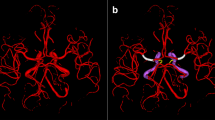

Yoshino M, Kin T, Shojima M, Nakatomi H, Oyama H, Saito N (2012) A high-resolution method with increased matrix size can characterize small arteries around a giant aneurysm in three dimensions. Br J Neurosurg 26(6):927–928

Kin T, Nakatomi H, Shojima M, Tanaka M, Ino K, Mori H, Kunimatsu A, Oyama H, Saito N (2012) A new strategic neurosurgical planning tool for brainstem cavernous malformations using interactive computer graphics with multimodal fusion images. J Neurosurg 117(1):78–88